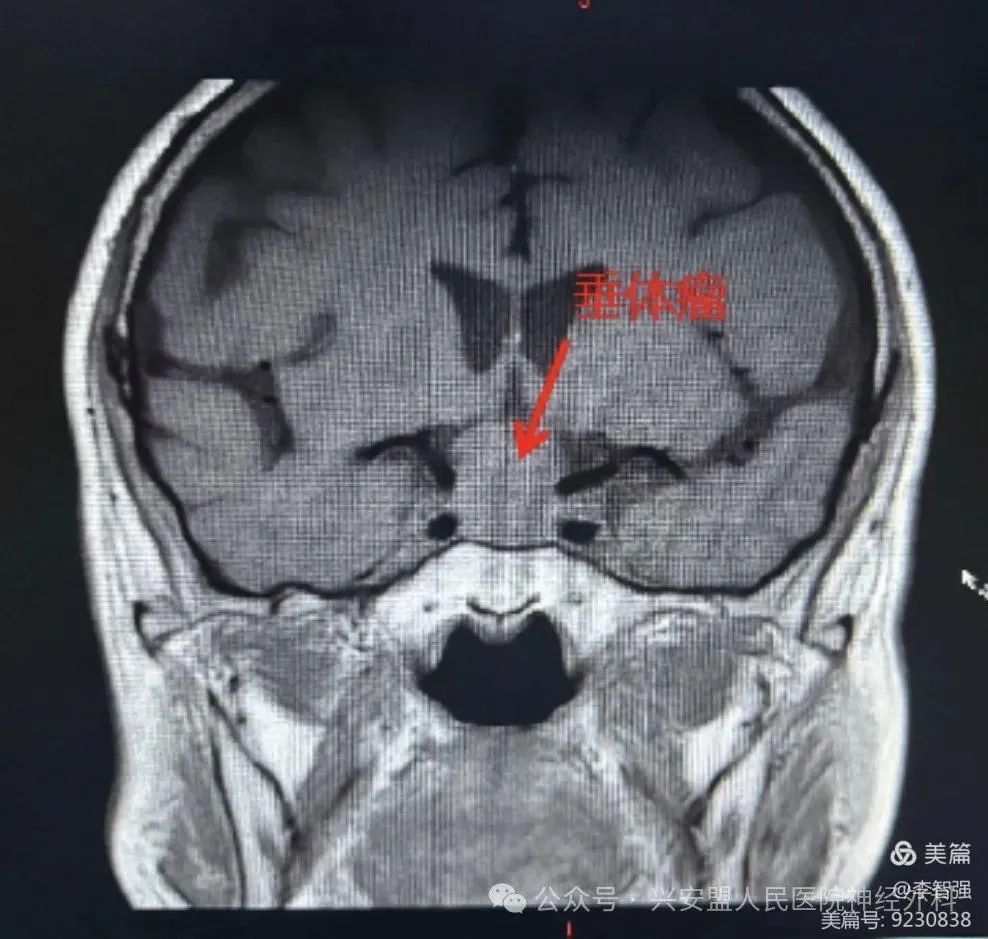

患者头颅核磁提示鞍区较大椭圆形病灶,视神经受压、上抬。

头颅核磁及头颅CT骨窗可见气化不良的甲介型鞍底